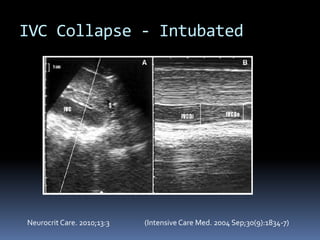

IVC Collapse - Intubated

Neurocrit Care. 2010;13:3 (Intensive Care Med. 2004 Sep;30(9):1834-7)

IVC Collapse -Intubated Neurocrit Care. 2010;13:3 (Intensive Care Med. 2004 Sep;30(9):1834-7)